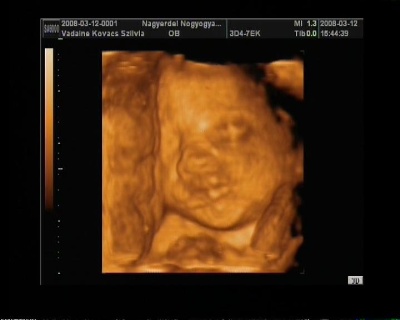

A doki szerint pufók kislány